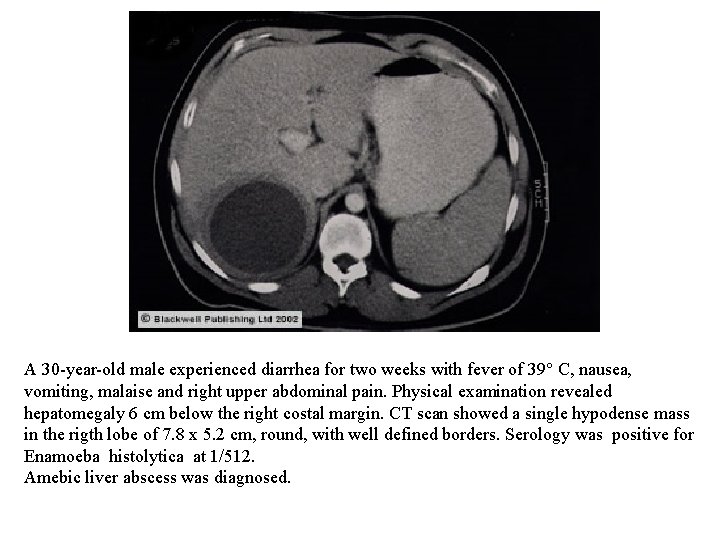

A 30 -year-old male experienced diarrhea for two weeks with fever of 39° C, nausea, vomiting, malaise and right upper abdominal pain. Physical examination revealed hepatomegaly 6 cm below the right costal margin. CT scan showed a single hypodense mass in the rigth lobe of 7. 8 x 5. 2 cm, round, with well defined borders. Serology was positive for Enamoeba histolytica at 1/512. Amebic liver abscess was diagnosed.